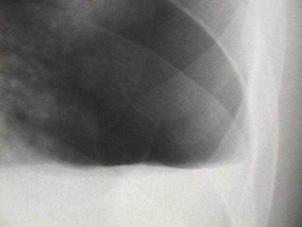

Pneumotorace sufocant bilateral Pneumotorace sufocant stang

Pneumotorace

sufocant stang Pneumotorace

sufocant drept Pneumotorace

sufocant drept